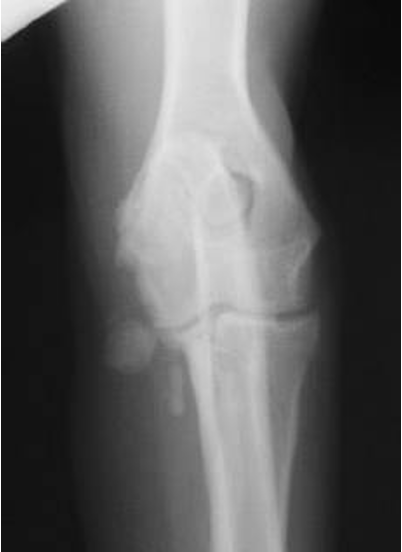

which OCD lesions are these in the dog

A = cd humerus

B = medial humeral condyle (elbow)

C = medial trochlear ridge (ankle)

D =lateral femoral condyle (knee)

Dog OCD signalment

young giant breed (6-9 mo age)